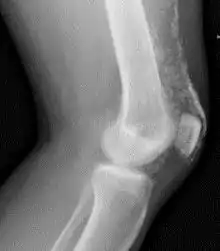

Magnetic resonance imaging may be useful to guide muscle biopsy and to investigate involvement of internal organs;[12] X-ray may be used to investigate joint involvement and calcifications.[13]